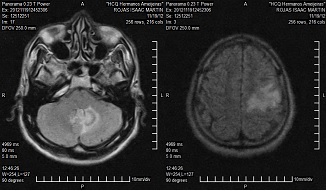

Resonancia magnética nuclear (RNM) de cráneo, 20 de noviembre de 2012: existen dos lesiones expansivas, una región fronto-parietal que mide 16 x 17 mm, rodeada de edema que no muestra efecto de masa, la otra ubicada hacia el cerebelo hemisferio izquierdo que mide 19 x 17 mm con edema (imagen 1).

IMAGEN 1. RNM de cráneo: 20 de noviembre de 2012